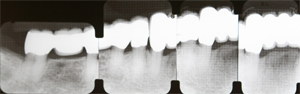

初診時のレントゲンです。上下顎とも歯周病が進行しており、根の先まで骨が吸収している歯もあります。

再生療法後1年

再生療法後1年で歯周組織を確認しました。骨欠損部が改善されています。

最終補綴

最終の被せ物を装着しました。レントゲンでも骨の凹みが改善されていることがわかります。

全額最終補綴

上顎はブリッジ及び義歯、下顎はブリッジ及びインプラント